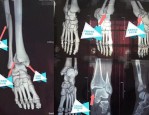

欧洲杯期间崴脚致小腿骨折,足球迷就医需谨慎

极目新闻记者 赵雪纯 通讯员 王竹君 阮晓芳 欧洲杯不仅“点燃”了球迷的心,也让更多人奔向绿茵场一展身手。原本有伤在脚的向先生(化姓)按捺不住内心的激动,趁欧洲杯比...